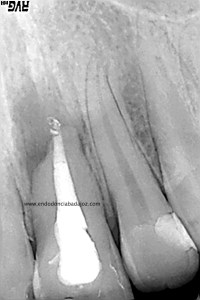

La paciente fue llamada a revisión al año:

Y más tarde, a los dos años:

Esta paciente nos llegaba sin sintomatología, y la lesión ha regenerado correctamente, con lo que podemos decir que hemos tenido éxito en el tratamiento.